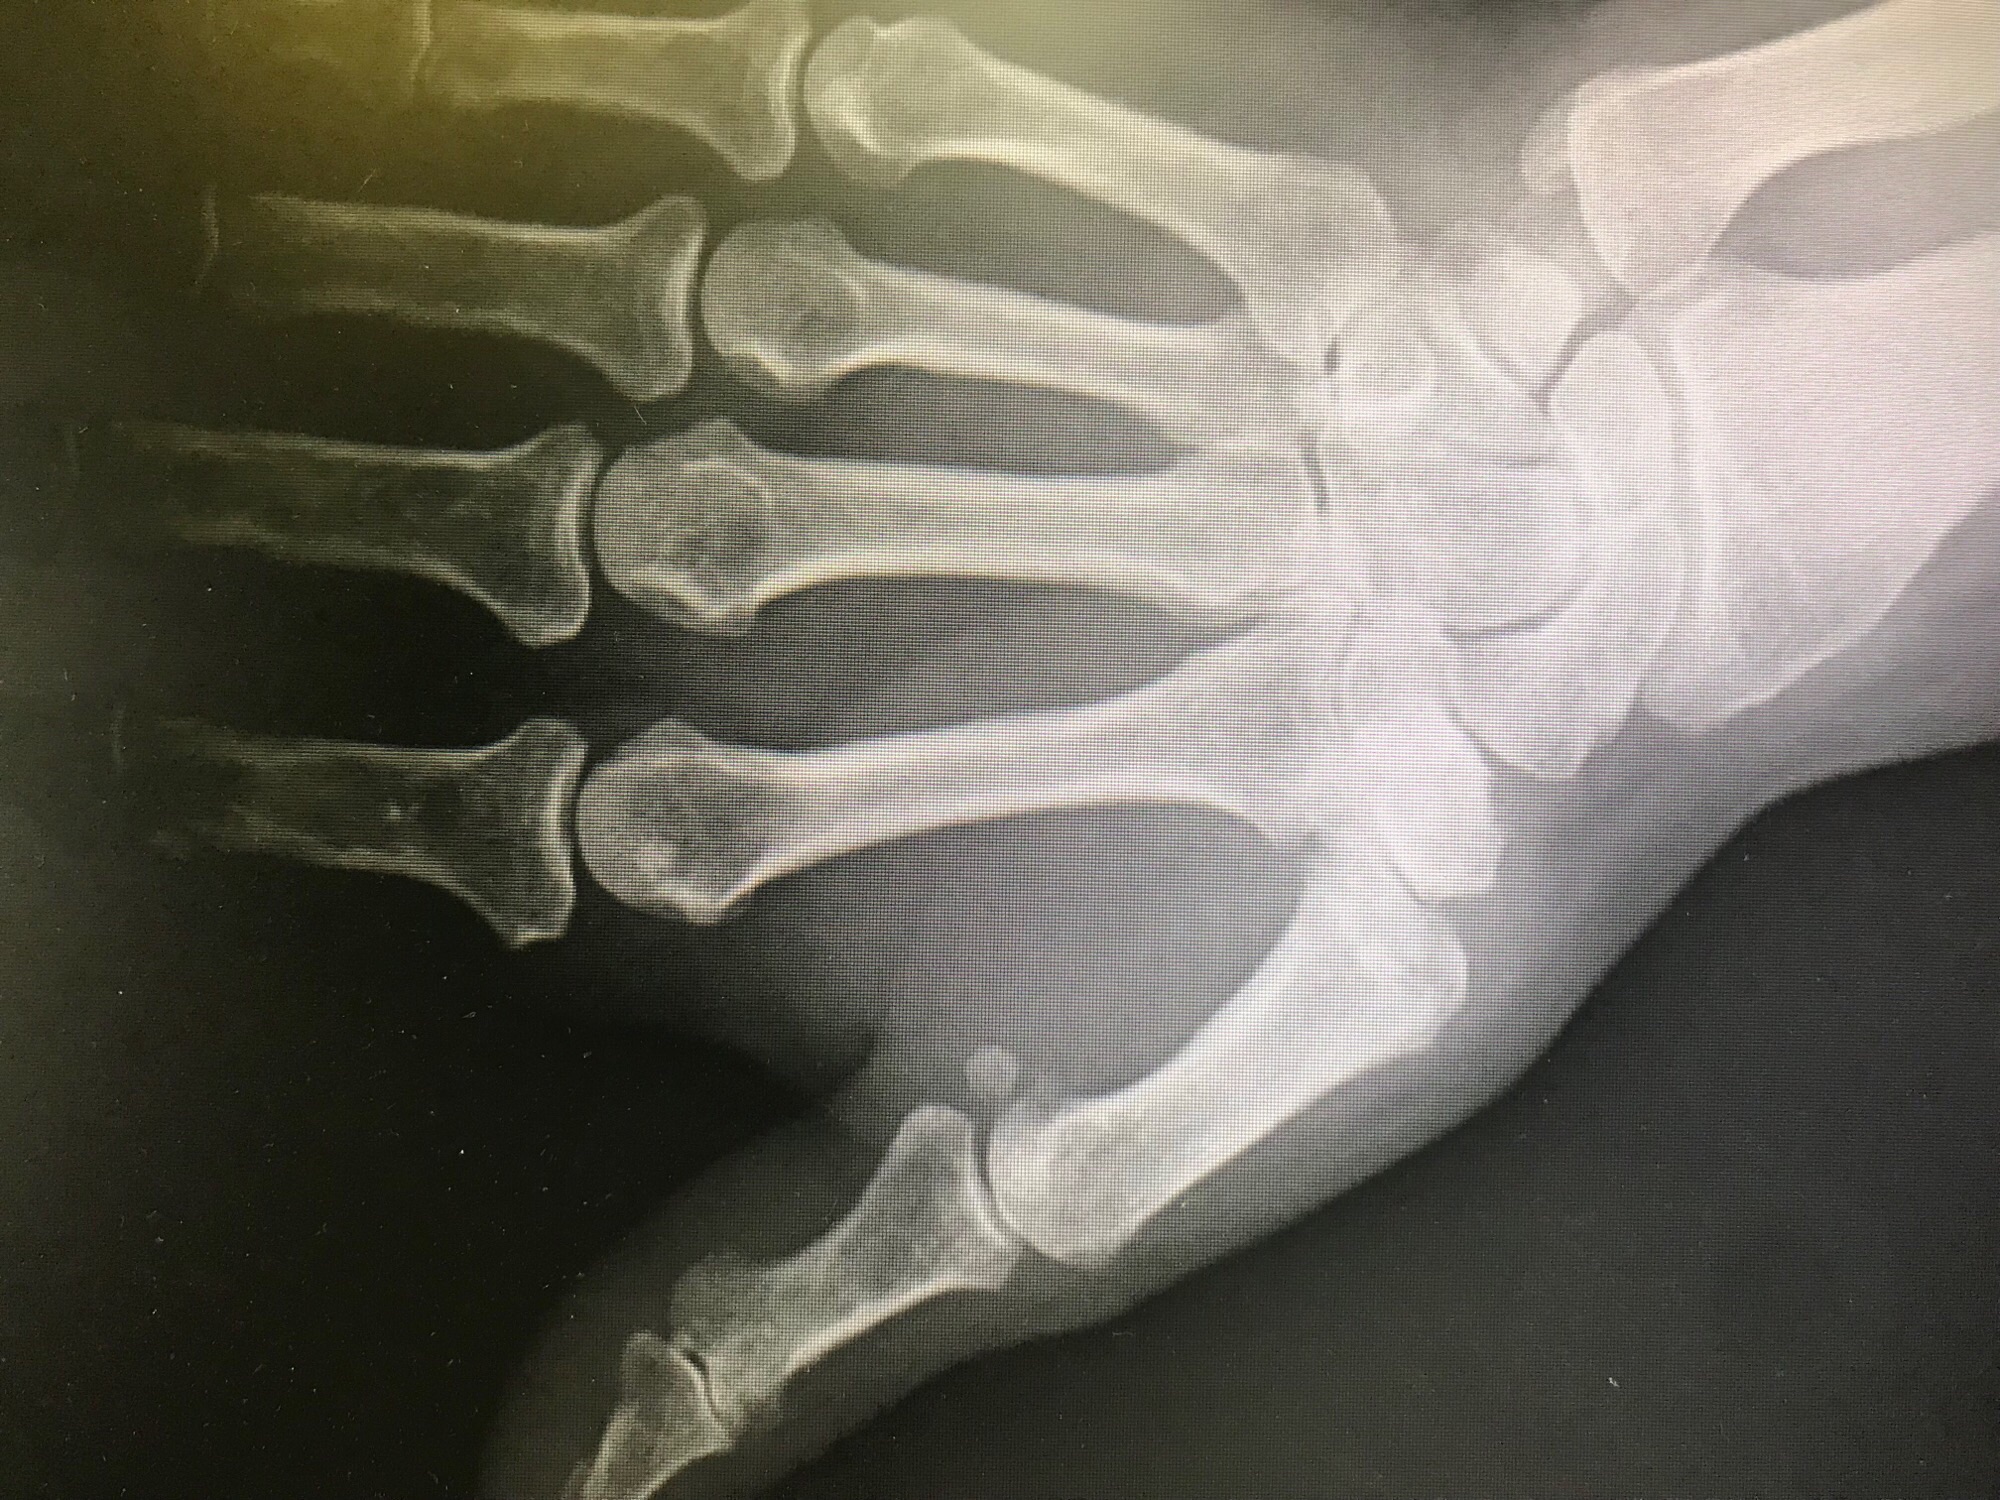

Rheumatoid arthritis affects the cells that line and normally lubricate the joints. This is a systemic condition which affect the whole body, and may affect multiple joints, usually on both sides of the body. The synovium becomes inflamed and erodes the cartilage and bone. The swollen tissue may also stretch the surrounding ligaments resulting in deformity and instability. The inflammation may also spread to the tendons, this resulting in stretching out of and ruptures of the tendons. Rheumatoid arthritis of the hand is most common in the wrist and the finger MP and PIP joints

Rheumatoid arthritis affects the joints (synovial tissue). It is a systemic disease, which means that it can affect many joints, usually in a symmetrical manner. The synovial joint becomes inflamed, and erodes the cartilage and bone. This hypertrophic synovium, due to its growing volume, will also occupy more space than available within the joint. This will cause tensioning of the ligaments and the articular capsule surrounding it and distort them, which will result in deformation and instability of the joints. Inflammation progressively erodes the tendons and can lead to their rupture. This rupture can also occur by a phenomenon of friction of the tendons on the deformed bone structures. Rheumatoid arthritis of the hand is more commonly seen in the joints of the wrist and fingers. The joints that are most often affected by rheumatoid arthritis are the hands, wrists, feet, ankles, knees, shoulders and elbows. The disease usually causes symmetrical inflammation of the joints of the body. The symptoms are:

- Pain.

- Morning stiffness.

- Inflammation of the joints.

- Decreased movement.

- Deformity of the joints.